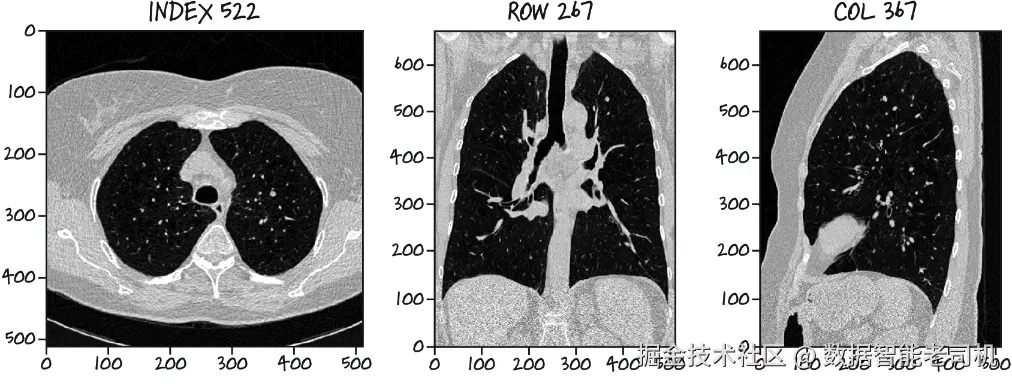

你能在图 11.5 的三个视图中找出那个被标记为结节的白点吗?(这个样本的 series_uid1.3.6.1.4.1.14519.5.2.1.6279.6001.126264578931778258890371755354,如果你之后想更仔细地查看它,这个信息会有用。)

image.png

图 11.5 一张 CT 扫描中,大约有 1,000 个结构在未经训练的人眼看来都像肿瘤。经由人工专家审阅后,其中恰好只有一个被识别为结节。其余的都是正常的解剖结构,例如血管、病灶以及其他无害的小块组织。

如果你需要提示,可以利用索引、行、列这几个值来帮助定位相关的高密度组织小块。你觉得自己能够仅凭这样的图像(而且仅仅是图像——没有索引、行、列信息!)推断出肿瘤的相关特征吗?如果给你的是完整的三维扫描,而不是仅仅三张穿过感兴趣区域的切片呢?

注意:如果你找不到那个肿瘤,也不必焦虑!我们就是想说明:这类数据是多么微妙。正因为它在视觉上很难识别,这个例子才成立。